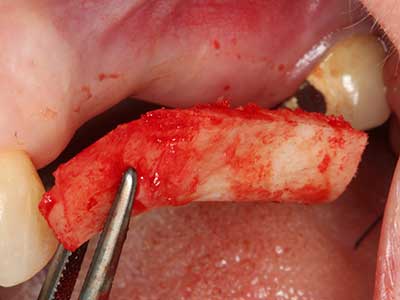

Indication: Autologous bone harvesting

Autologous bone transplants are used in the form of blocks, shells, rings and are also combined with bone replacement materials as chips. If the implant site is prepared at the same time as the augmentation, various bone filter systems have proven effective for collecting the resulting bone chips. As an alternative, the implant site can be prepared using a low-speed device without irrigation. If an implant is not inserted, bone chips can be harvested from the periphery with bone scrapers. This is also possible with piezo surgery using specialized attachments that yield higher-quality bone chips compared chips harvested with round drills, as has been confirmed in a study comparing the two methods (Chiriac, Herten et al. 2005).

Piezo surgery has additional advantages when harvesting bone blocks. In addition to the high precision with osteotomy described above, the use of the thin saw tips specifically minimizes loss of material. Greater loss of material during harvesting can be expected with the thicker instrument tips, particularly when using Lindemann drills (Lakshmiganthan, Gokulanathan et al. 2012). The basal separation, which is necessary particularly for retromolar block transplants, is simplified by specially designed rectangular saws, with the result that piezo surgery is viewed as a precise, simple and safe procedure for harvesting retromolar bone blocks (Happe 2007) (Fig. 1-12).